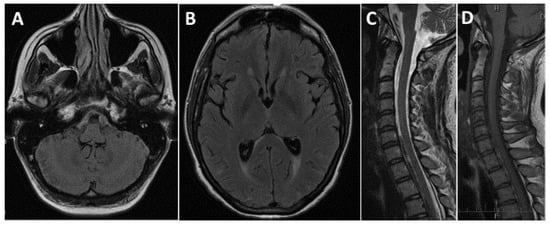

2. Case Report